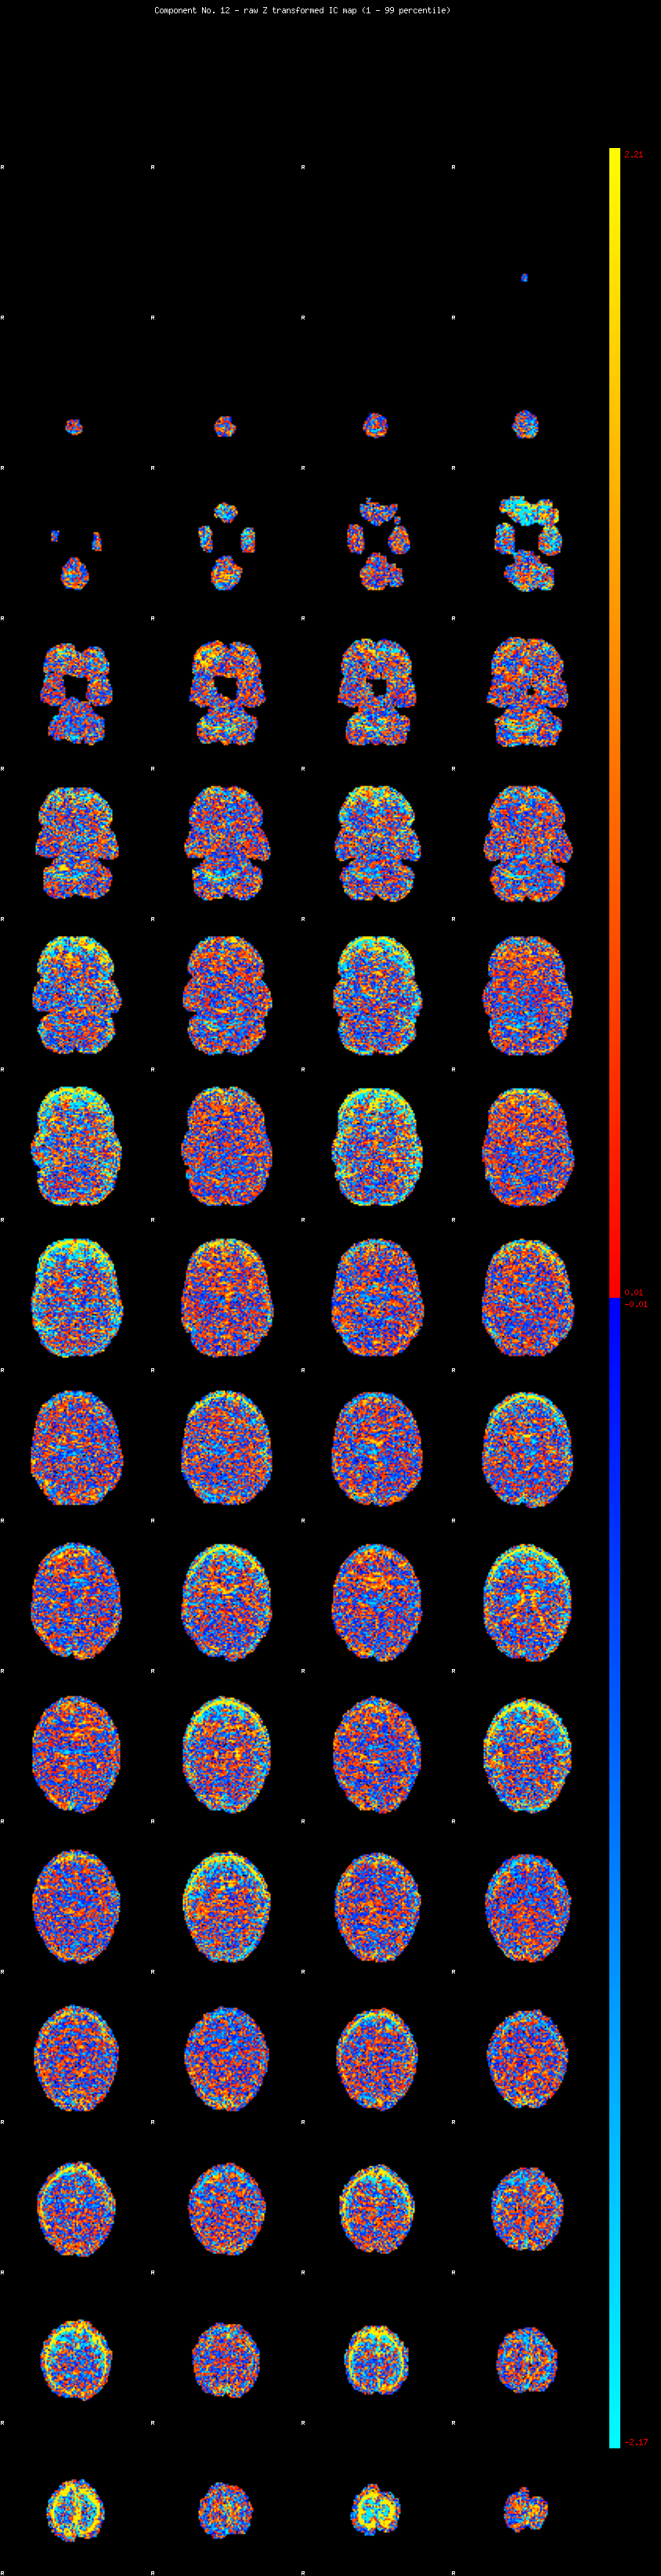

IC_12 Mixture Model fit

Means : -0.000000 3.877906 -2.769442

Vars : 1.000000 7.443557 3.025693

Prop. : 0.915892 0.037857 0.046251